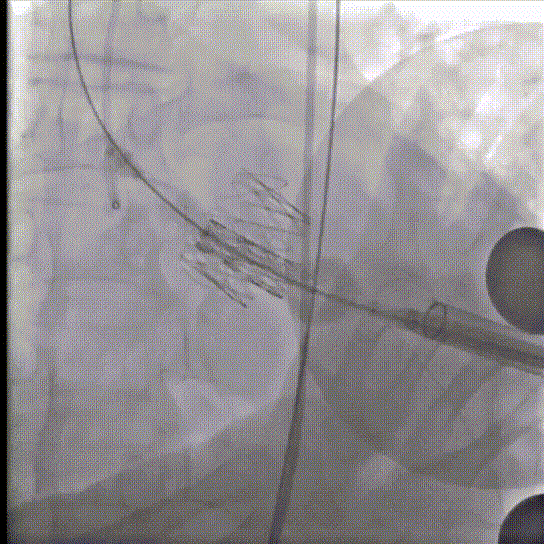

术前经详尽评估患者病情,通过CT重建观察到既往植入的自膨式TAVR瓣膜呈椭圆形,测量瓣环直径,及双侧冠脉开口高度,并评估外周血管入路。由于患者外周血管钙化严重且迂曲,经外周血管途径有较大风险,决定对该病例采用经心尖途径行TAVR瓣膜内 “瓣中瓣”手术。但第二次经心尖途径又将面临心脏、肺、胸壁肌肉组织的粘连,手术难度大。经术前反复讨论和仔细测量毁损TAVR瓣膜的平均内径和冠脉开口高度,决定选用25号 Renato球扩瓣膜。Renato球扩式瓣中瓣可以提供更强的径向支撑力,瓣架高度低,术前模拟植入评估显示冠脉梗阻风险低。手术过程顺利,最终瓣中瓣植入位置理想,功能表现出色,主动脉根部造影及经食道超声观察无瓣中及瓣周反流。